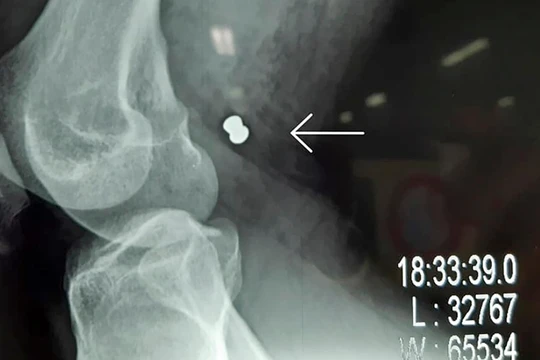

VietTimes – Sau 5 tiếng đồng hồ phẫu thuật và truyển hết 1,5 lít máu, êkíp các bác sĩ Bệnh viện Vĩnh Đức (Quảng Nam) đã cứu sống bệnh nhân bị súng hơi bắn đứt động mạch và tĩnh mạch đùi.